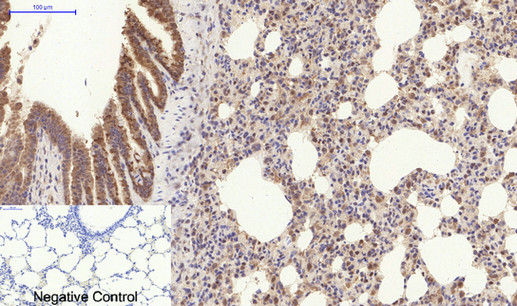

Immunohistochemical analysis of paraffin-embedded Rat-lung tissue;

1.COL1A2 Polyclonal Antibody was diluted at 1:200(4℃,overnight);

2.Sodium citrate pH 6.0 was used for antibody retrieval(>98℃,20min);

3.Secondary antibody was diluted at 1:200(room tempeRature, 30min). Negative control was used by secondary antibody only.